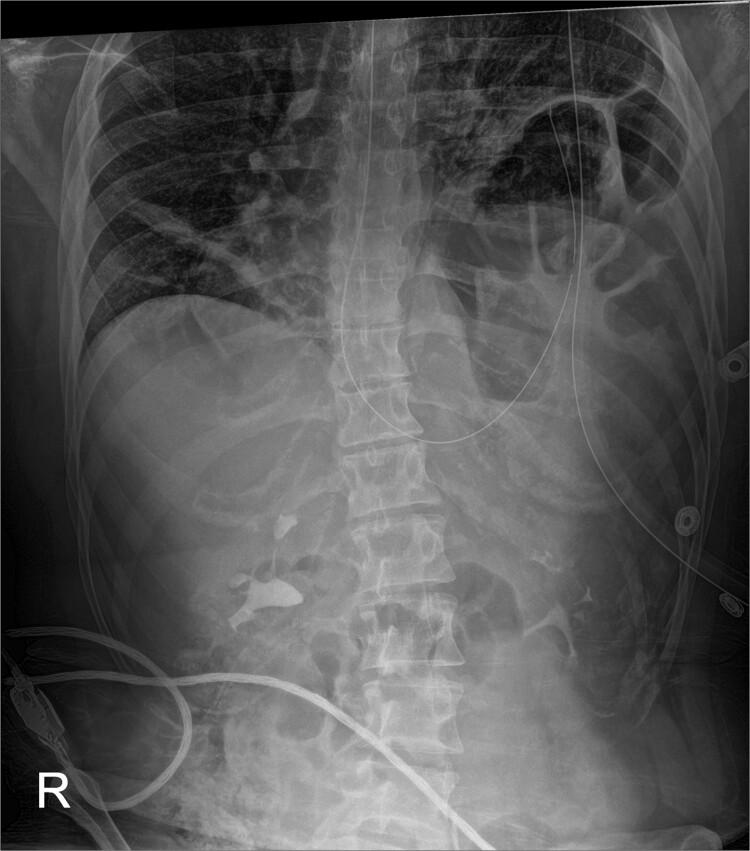

Gastric volvulus has been rarely associated with diaphragmatic paralysis or eventration. In this article, we present the case of a patient with idiopathic paralysis of the left hemidiaphragm that underwent treatment with a robotic thoracoscopic diaphragm plication, which was complicated by massive gastric volvulus resulting in such significant intra-abdominal hypertension that the ipsilateral diaphragm ruptured anterior to the plication suture line.

胃扭转很少与膈麻痹或膈膨出相关。在本文中,我们报告了一例特发性左半膈麻痹患者,该患者接受了机器人胸腔镜膈折叠术治疗,术后并发大量胃扭转,导致严重的腹腔内高压,使得同侧膈肌在折叠缝线前方破裂。